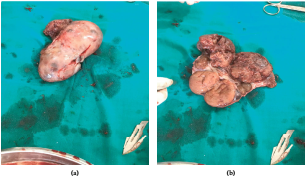

患者的产前检查显示,正处于分娩的潜伏期,被留院观察。在积极开始分娩后,被转移到分娩病房,但分娩进展很差,并准备进行紧急剖宫产。术中取出一名体重3.5 kg,Apgar评分为9-10分的健康女婴(无男性化特征)。在修复子宫过程中,在左侧附件发现一个巨大的肿块,大约为9cmx7cmx5.5cm,累及左侧卵巢(图1a-d),并进行了单侧卵巢切除术。将整个卵巢组织(图2a-b)送去进行组织病理学评估,怀疑卵巢恶性肿瘤。子宫和右卵巢大体正常。

图1.(a-d)左卵巢明显增大;(b)增大的左卵巢(LO)与子宫(U)的关系

图2.(a,b)增大的左卵巢切除后